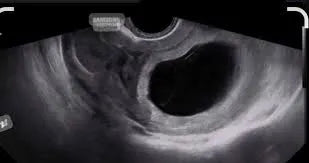

Réserve Ovarienne Faible : Causes, Symptômes, Traitements et Solutions La réserve ovarienne faible est une préoccupation majeure pour les femmes qui souhaitent concevoir. Elle reflète le nombre d'ovocytes encore disponibles...